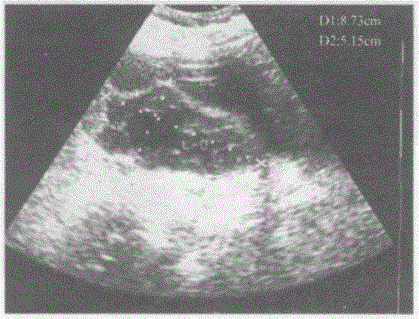

问题 临床资料:女,40岁,自述下腹痛15天。妇科内诊:子宫左上方可扪及拳头大肿物,质中等,活动度差。 超声综合描述:左附件区可见8.7cm×5.1cm低回声区,包膜显示欠清晰,形态不规则,中部可见形态不规则无回声区。 超声提示:

选项 A.左卵巢转移癌 B.左卵巢宫外孕 C.左卵巢癌 D.左卵巢巧克力囊肿

答案 C